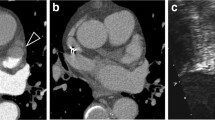

Deidentified thin-section CT image data were exported offline in digital imaging and communications in medicine (DICOM) format and processed with a standalone research radiomics prototype (FRONTIER, Siemens Healthineers) [14]. A post-doctoral research assistant (1-year experience) segmented the entire LAA in the early phase CT images with the manual segmentation tool. A free-hand ROI was drawn to segment the entire LAA volume. The prototype then calculated 1691 radiomic features from the segmented volume of interest (Fig. 1). Calculated radiomics comprised first-order, shape-based, and texture encoding features (n = 110), including the gray level co-occurrence matrix (GLCM), gray level run length matrix (GLRLM), gray level size zone matrix (GLSZM), neighboring gray-tone difference matrix (NGTDM), and gray level dependence matrix (GLDM). Besides these, the prototype calculated square, square root, logarithm, and exponential of the mentioned features (n = 372). To evaluate the spatial time–frequency of the two-dimensional images, 3-D wavelet transform parameters (n = 744) were used with the following subdivisions: HHH, HHL, HLL, HLH, LLH, LHL, LHH, LLL. Log with five (1.5 mm) sigma level (n = 465) of the radiomics classes was also retrieved. Further information on these radiomics is available on the following website (https://pyradiomics.readthedocs.io/en/latest/features.html accessed on October 28, 2020).

Early-phase (a, e, i) and late-phase (b, f, j) transverse CT images of three patients including a 52-year-old male with LAA contrast mixing artifact (a, b), a 75-year-old male with a LAA thrombi (e, f), and a 63-year-old male with homogenous LAA opacification (i, j). Following manual segmentation of LAA (c, g, and k), the radiomics prototype created a three-dimensional volume of interest to estimate radiomics (d, h, and l)